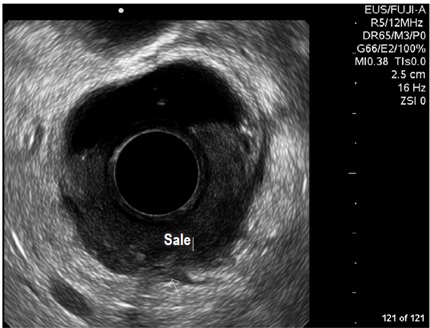

Para todos los exámenes se utilizó un endosonógrafo radial estándar con visión endoscópica y endosonográfica en el mismo equipo. Se utilizaron frecuencias entre 5 y 15 MHz, según la necesidad. El procesador de la unidad utilizado es de alta resolución.

Por estudio de incontinencia fecal se encontraron 44 pacientes (32,35%); la mayoría fueron mujeres (86%, n =38) (tabla 2 y figura 1). Las indicaciones de fístula perianal y absceso perianal tuvieron una frecuencia de 12,5% y 6,62%, respectivamente. Dentro del grupo de incontinencia, 28 de las 38 mujeres que la reportaron también tenían historia de desgarro obstétrico (76,7%). El total de las indicaciones está resumido en la tabla 3.

Diagnóstico endosonográfico final

Se encontró defecto de los esfínteres en 40 pacientes (29,41%), de los cuales 6 fueron hombres y 34 mujeres; aquí cabe anotar que el 93,33% (n =28) de las mujeres que tienen historia de incontinencia, también tienen antecedente de desgarro. De las 34 mujeres con defectos en los esfínteres, 32 lo tuvieron localizado en canal anal medio, con compromiso en nivel anterior, 1 de ellas con atrofia difusa de esfínteres, y otra con compromiso de canal anal inferior (figura 2).

Por otro lado, en el grupo masculino con estudio por incontinencia, el diagnóstico en todos fue cambios por atrofia del aparato esfinteriano, que pudo verse en cualquiera de las localizaciones del canal anal y que se evidenció como engrosamiento de los músculos en general y cambios difusos de la ecogenicidad de los mismos, sin posibilidad de determinar el borde que los delimita. Se encontró fístula perianal en 16 pacientes (11,8%); la principal forma de presentación de las fístulas fue transesfintérica (37,5%), seguida por las interesfintéricas y anovaginales (figuras 3 y 4). Doce pacientes presentaron absceso perianal (8,8%); de estos, el 83% correspondió a abscesos submucosos o isquiorrectales (figura 5).